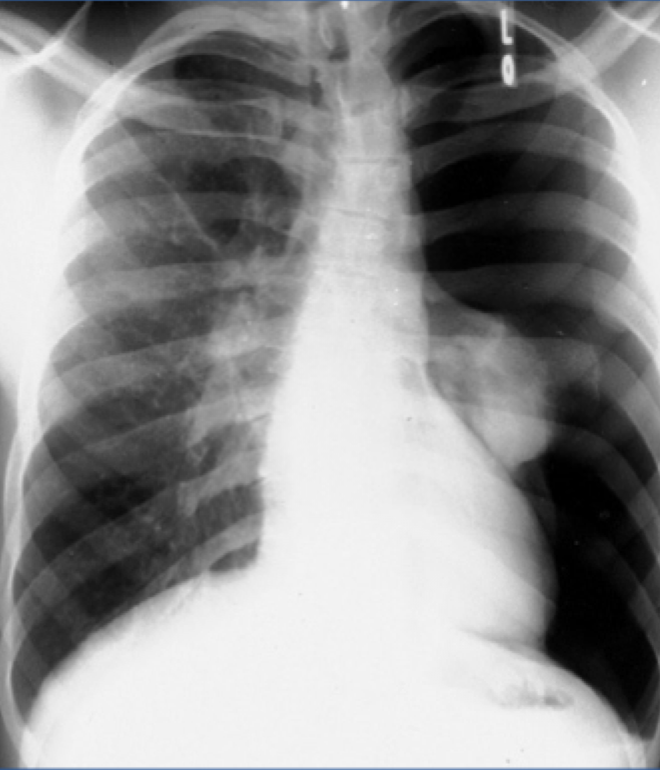

Tension pneumothorax:

-Large amount of air in the affected hemithorax and CONTRALATERAL shift of the mediastinum